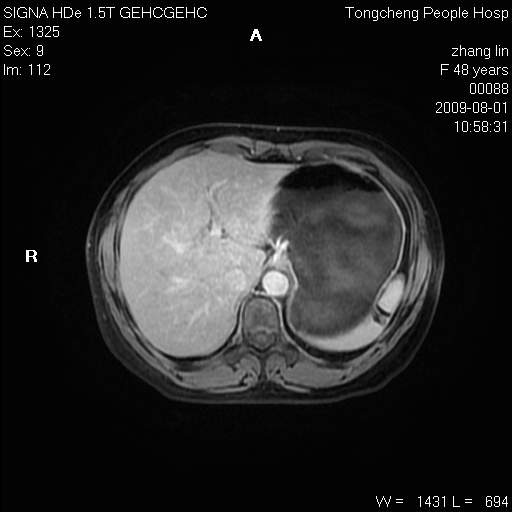

女,48岁。健康体检,彩超发现右肾占位性病变。平素健康。

临床诊断:右肾占位性病变,性质待定(囊肿?肿瘤?)。

上中腹部mr平扫+增强扫描,图像如下:

右肾上极见一类圆形病灶,t1wi呈等信号t2wi呈等高混杂信号,三期增强无强化,边界清---考虑囊肿出血。

同反相位均表现为等信号,病变无强化,考虑含蛋白的囊肿可能,弥散加权相或许有些帮助,